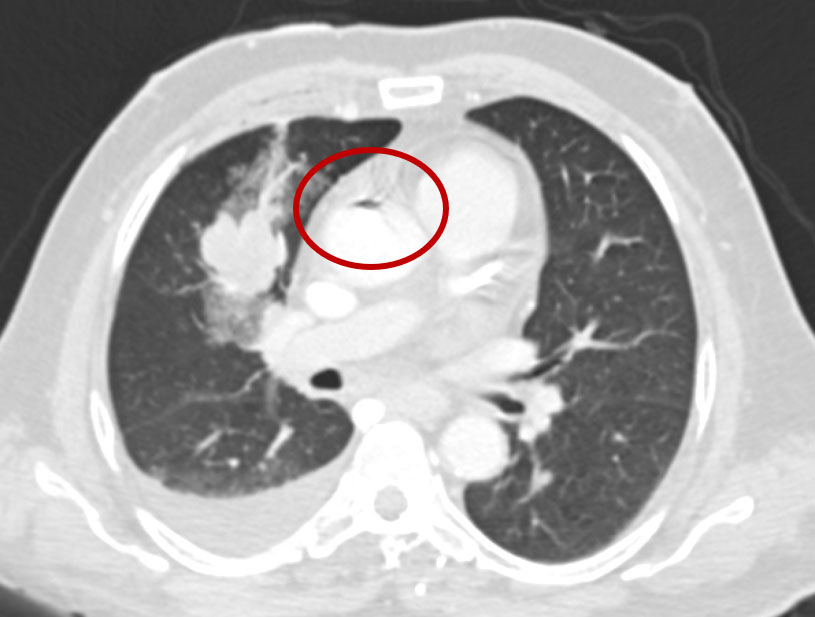

Non-contrast Thorax:

Focus of air in the ascending aorta